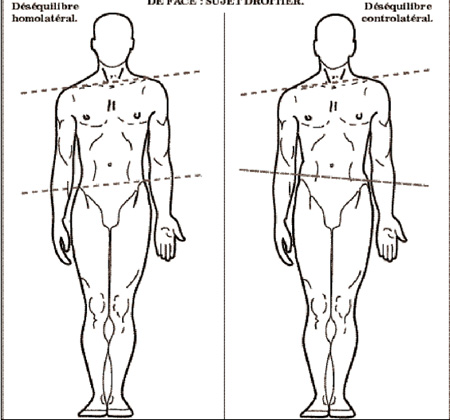

Integrative Neurosomatic Therapy is a structurally integrative approach to pain relief. It’s a way to analyze and thoroughly explore the muscles, tendons, and ligaments in order to find hidden sources of pain.

My goal is to help clients eliminate pain and to educate them on ways to prevent reoccurring injuries. When proper structure is restored to the body, the accompanying problems are often alleviated.